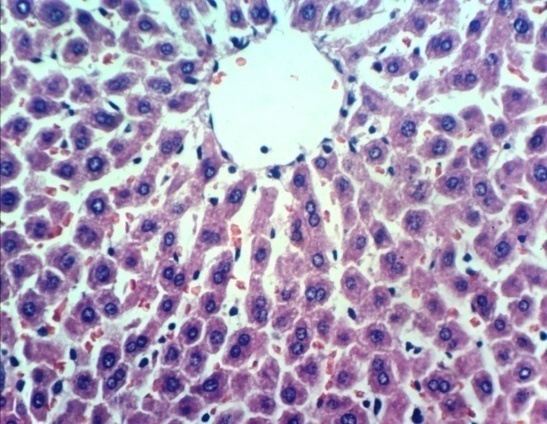

Liver histology

Microscopically, liver of normal control rats revealed the normal histological structure of hepatic lobules (photomicrograph 5). Meanwhile, liver of diabetic rats showed Kupffer cells activation, cytoplasmic vacuolization of hepatocytes, cystic dilatation of bile duct and fibroblasts proliferation in the portal triad around the bile duct (photomicrographs 6a and 6b).

The improved picture was noticed in the liver of rat from diabetic rats treated with H. pluvialis extract, the examined sections revealed slight congestion of hepatic sinusoids and activation of Kupffer cells (photomicrograph 7).

Moreover, improved liver sections were noticed in the rat from diabetic rats treated with glibenclamide drug, some examined liver revealed congestion of central vein and hepatic sinusoids as well as activation of Kupffer cells (photomicrograph 8a), whereas, other sections showed no changes except slight activation of Kupffer cells (photomicrograph 8b).

| Photomicrograph 5: Liver of normal control rats showing the normal histological structure of hepatic lobule (H and E X 400) | Photomicrograph 6a: Liver of diabetic rats showing Kupffer cells activation and cytoplasmic vacuolization of hepatocytes (H and E X 400) | Photomicrograph 6b: Liver of diabetic rats showing cystic dilatation of bile duct and fibroblasts proliferation in the portal triad around the bile duct (H and E X 400) |

| Photomicrograph 7: Liver of diabetic rats treated with H. pluvialis extract showing slight congestion of hepatic sinusoids and activation of Kupffer cells (H and E X 400) | Photomicrograph 8a: Liver of diabetic rats treated with glibenclamide drug showing congestion of central vein and hepatic sinusoids as well as activation of Kupffer cells (H and E X 400) | Photomicrograph 8b: Liver of diabetic rats treated with glibenclamide drug showing slight activation of Kupffer cells (H and E X 400) |